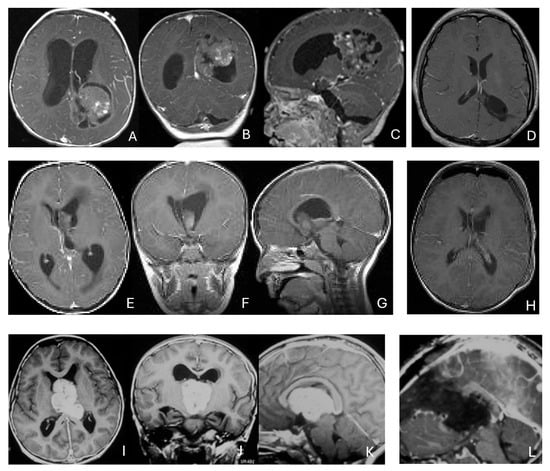

Objectives: Atypical teratoid/rhabdoid tumors (ATRTs) are rare, malignant central nervous system (CNS) neoplasms that predominantly affect infants and young children. While ATRT arises throughout the CNS, its extracranial counterpart, malignant rhabdoid tumor, occurs in other organs. A single-institutional cohort is reviewed to map

Objectives: Atypical teratoid/rhabdoid tumors (ATRTs) are rare, malignant central nervous system (CNS) neoplasms that predominantly affect infants and young children. While ATRT arises throughout the CNS, its extracranial counterpart, malignant rhabdoid tumor, occurs in other organs. A single-institutional cohort is reviewed to map anatomic distribution of pediatric ATRTs and to integrate a literature review to contextualize ATRT histogenesis from anatomical and embryological perspectives. Methods: A retrospective review was conducted on a cohort of 50 pediatric patients with ATRT treated over 20 years. Demographic, surgical, and neuroimaging data were correlated to define tumor location, extent, and compartmental involvement. A focused literature review synthesized molecular subclassifications and proposed cells of origin/cytogenesis. Results: Of the 50 ATRTs, 18 (36%) were infratentorial, 15 (30%) supratentorial, 11 (22%) in the pineal region, and 6 (12%) in the spinal compartment. Among infratentorial tumors, 10 were centered in the fourth ventricle, with or without extension into the cerebellopontine angle (CPA) cistern; the remainder arose in the CPA. Among ATRTs of the cerebral hemispheres, 3 showed bi-hemispheric involvement crossing the falx cerebri. ATRTs of the pineal region predominantly originated from the superior medullary velum. These topographic data were corelated with embryological and molecular information available in the literature. Conclusions: ATRTs arise across diverse neuroanatomical compartments—including intraparenchymal, intraventricular, extra-axial, and extradural sites—underscoring biological heterogeneity. Inactivation of SMARCB1 is the defining molecular event and principal oncogenic driver, although the upstream mechanisms precipitating these alterations remain incompletely resolved. Molecular subgroups—ATRT-TYR, ATRT-SHH, and ATRT-MYC—display distinct age distributions and anatomic predilections, implicating developmental context in tumor initiation. The characteristic cellular admixture of rhabdoid cells with mesenchymal and/or epithelial differentiation, together with intra- and extra-axial and occasional extradural presentations, supports a model in which at least a subset of ATRTs may originate from neural crest-derived lineages, despite little or no neural crest contribution to brain parenchyma development. Neural plate border progenitors with bipotent features represent a plausible intraparenchymal cell of origin. Definitive resolution of these origins and the mechanisms of SMARCB1 disruption will require integrated approaches. Further investigations are warranted to clarify these mechanisms.